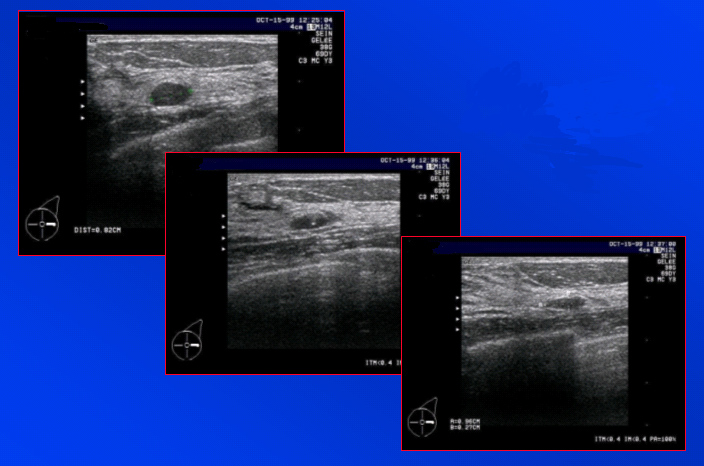

Vidange d’un kyste à contenu épais | Iconographie précédente | Retour cours | Index iconographique | Iconographie suivante |